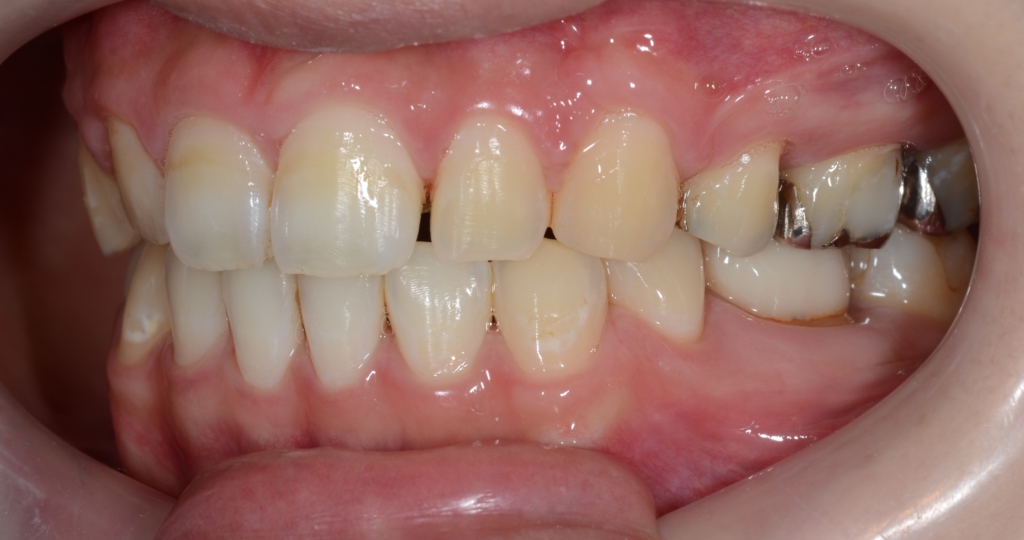

【After】

変な悪目立ちをするものはありません

装置を外す準備をした時点では無かったのに、外した時点で隙間が生じてしまいました。

もちろん、この後に部分的に再矯正治療をして、隙間を閉じたうえで改めて治療を終えています。